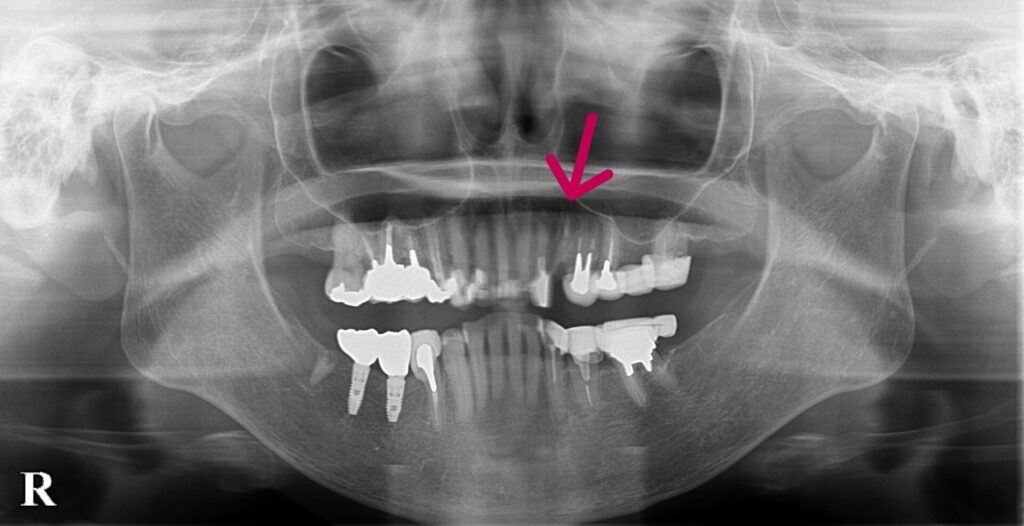

左上3歯根破折のため抜歯。

抜歯と同時にインプラント埋入。その日のうちに仮歯まで装着します。切開縫合を行わないため腫脹、痛みの少ない患者さんにやさしい術式になります。

左上3歯根破折。右下56は当院にてインプラント埋入

抜歯と同時にインプラント埋入。サージカルガイドを使用することにより正確な位置に埋入可能